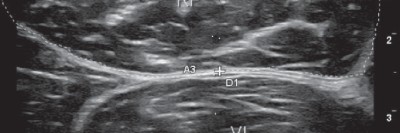

How to Sonografie: Schmerzen an Sprunggelenk und Fuß

Die Ursachen für Beschwerden des Sprunggelenks reichen von Instabilitäten, über Arthritiden bis hin zu Bandverletzungen oder Frakturen. Zur Abklärung kann die Arthrosonografie gute Dienste leisten. Anhand von Beispielen wird hier der richtige Umgang mit dem Schallkopf in den verschiedenen Schnittebenen erklärt.

Pincer-Konstellation, Hüftdysplasie und CAM-Impingement im Röntgenbild/© Fehske K / all rights reserved Springer Medizin Verlag GmbH, Sonographiequerschnitt über der Hälfte des M. quadriceps (Normalbefund)/© Gehlen M et al. / all rights reserved Springer Medizin Verlag GmbH, Mediale Meniskusallografttransplantation /© Winkler PW et al. doi.org/10.1007/s43205-025-00320-y unter CC-BY 4.0, Sehnentransplantate zur Rekonstruktion des vorderen Kreuzbands /© Fink C et al. doi.org/10.1007/s00113-025-01551-4 unter CC-BY 4.0, Knie-MRT zeigt überlastungsbedingte Knochenmarködeme/© Brockmeyer M et al. / all rights reserved Springer Medizin Verlag GmbH, Läufer umfasst sein Sprunggelenk/© PeopleImages / Getty Images / iStock (Symbolbild mit Fotomodell), Gruppe beim Rückentraining im Fitnesscenter/© Robert Kneschke / stock.adobe.com (Symbolbild mit Fotomodellen), Walking mit Kniebandage/© Suzi Media Production / Getty Images / iStock (Symbolbild mit Fotomodell), Vordere Kreuzbandruptur/© Springer-Verlag Berlin Heidelberg 2016, Operation zum Kniegelenkersatz/© Issara / stock.adobe.com, Ein kleines Kind hüpft auf einem Trampolin/© anzebizjan / stock.adobe.com (Symbolbild mit Fotomodellen), Anteriore Schulterluxation im Röntgenbild/© Spagna G et al. / all rights reserved Springer Medizin Verlag GmbH, Laufschuh binden/© ssoil322 / stock.adobe.com, Hämatom an der Stirn des 9-Jährigen/© Dr. med. Thomas Hoppen, Innenseitige Hauteinziehung bei eingeschlagenem Innenband/© Akalin ER et al. / all rights reserved Springer Medizin Verlag GmbH, Rekonstruktion der Halswirbelsäule im CT/© Prof. Klaus Schunk, Sonografie am Fußgelenk/© A. Schuh, Gebrochener Fuß im Gips/© Aleksandr Kirillov / stock.adobe.com (Symbolbild mit Fotomodell), Search Icon, Arthropedia, Frau unkenntlich fasst sich ans Knie/© Pornpak Khunatorn / Getty Images / iStock (Symbolbild mit Fotomodell), Ärzteteam führt Hüftoperation durch/© ATRPhoto / stock.adobe.com (Symbolbild mit Fotomodell)